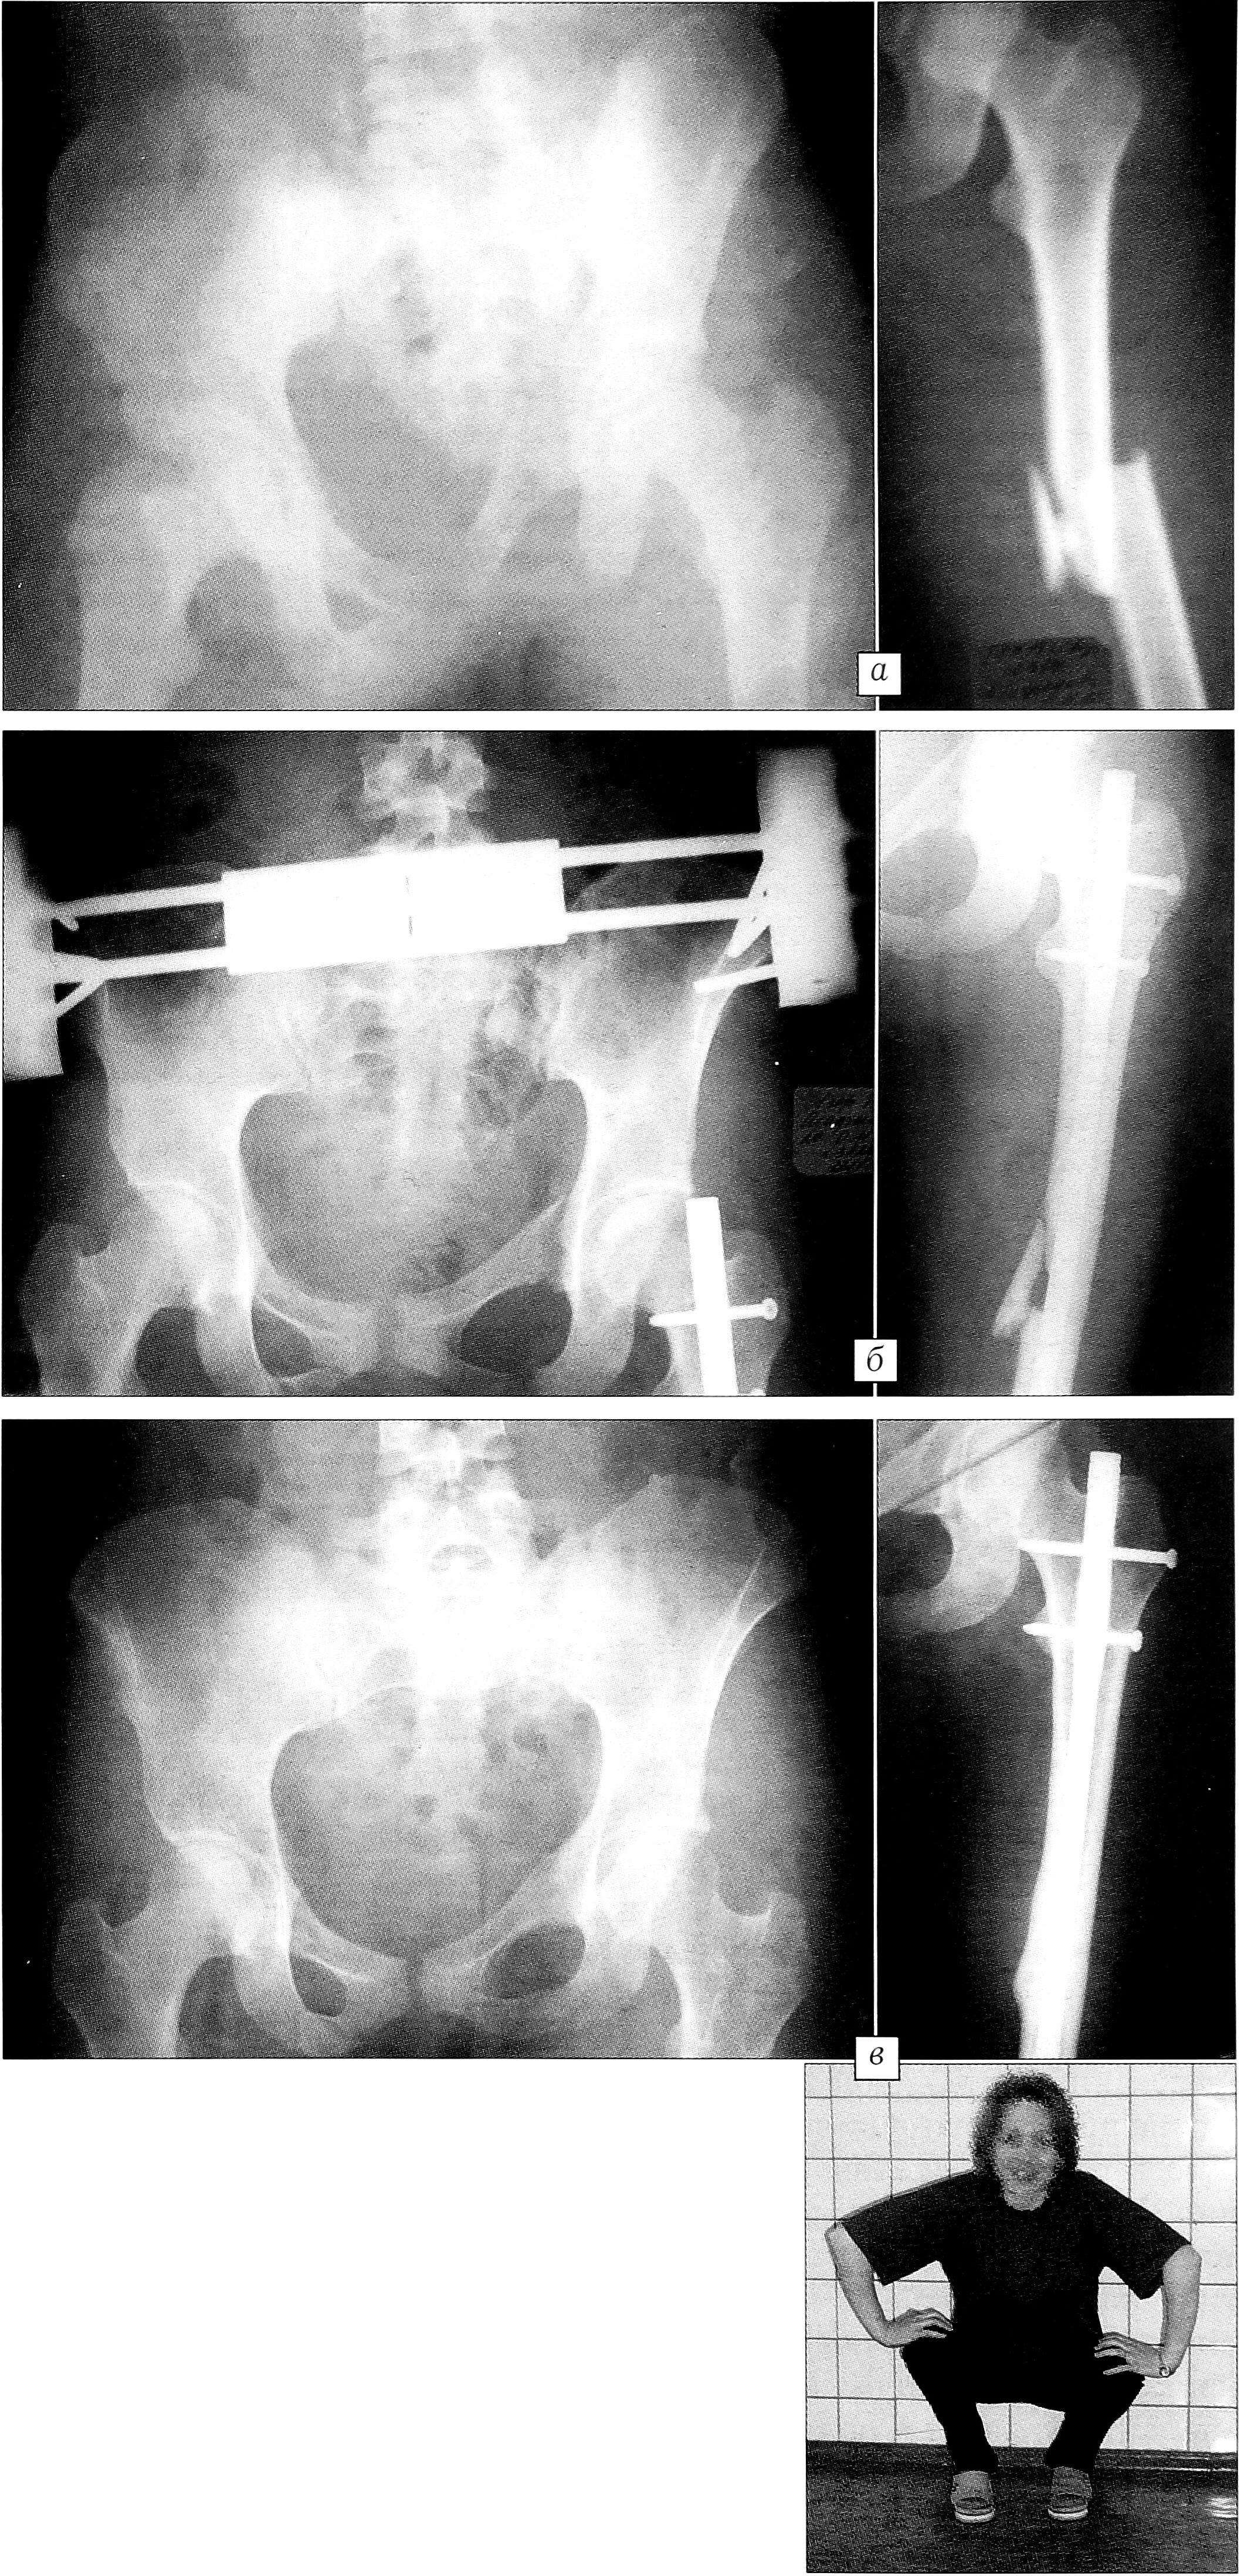

Пример. Больная А.,24 лет, поступила в клинику 26.04.00. Травму получила в результате автоаварии (была сдавлена между двумя автомобилями). При поступлении диагностирована тяжелая сочетанная травма: разрыв левого крестцово-подвздошного сочленения, перелом лонной и седалищной костей слева с вывихом левой половины таза; внутрибрюшинный разрыв мочевого пузыря; закрытый поперечно-оскольчатый перелом средней трети левого бедра со смещением отломков; сотрясение головного мозга (рис. 1, а). После проведения массивной противошоковой терапии, через 5 ч с момента травмы, одномоментно последовательно произведены: лапаротомия, ревизия брюшной полости и мочевого пузыря, ушивание разрыва мочевого пузыря, эпицистостомия; наложение стержневого аппарата на таз; закрытый блокирующий остеосинтез левого бедра стержнем UFN (рис. 1, б). Послеоперационный период протекал без осложнений. Эпицистостома удалена через 12 дней. Иммобилизация таза аппаратом продолжалась 6 нед. Полная нагрузка на левую ногу разрешена через 8 нед. Пациентка осмотрена через 4 мес: перелом бедра сросся. Через 1 год — полное функциональное восстановление (рис. 1, в).

Рис. 1. Больная А. 24 лет. Сочетанная травма. Разрыв левого крестцово-подвздошного сочленения, перелом лонной и седалищной костей с вывихом левой половины таза, закрытый поперечно-оскольчатый перелом левой бедренной кости со смещением отломков. а — рентгенограммы при поступлении; б — после операций; в — рентгенограммы и функциональный результат через 1 год.